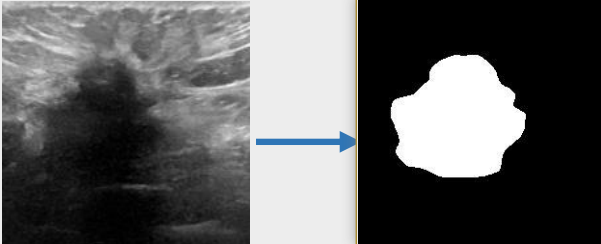

## 算法原理 U-KAN与其它图像分割算法一样,将图片数据送入模型后,依次通过预处理、特征提取,最后经过卷积预测出像素类别实现分割。

## 环境配置 ``` mv U-KAN-optimize_pytorch U-KAN # 去框架名后缀 # if torch>2.0, modify /usr/local/lib/python3.10/site-packages/timm/models/layers/helpers.py: from torch._six import container_abcs -> import collections.abc as container_abcs ``` ### Docker(方法一) ``` docker pull image.sourcefind.cn:5000/dcu/admin/base/pytorch:2.1.0-ubuntu20.04-dtk24.04.1-py3.10 # 为以上拉取的docker的镜像ID替换,本镜像为:a4dd5be0ca23 docker run -it --shm-size=32G -v $PWD/U-KAN:/home/U-KAN -v /opt/hyhal:/opt/hyhal:ro --privileged=true --device=/dev/kfd --device=/dev/dri/ --group-add video --name ukan bash cd /home/U-KAN pip install -r Seg_UKAN/requirements.txt # requirements.txt ``` ### Dockerfile(方法二) ``` cd U-KAN/docker docker build --no-cache -t ukan:latest . docker run --shm-size=32G --name ukan -v /opt/hyhal:/opt/hyhal:ro --privileged=true --device=/dev/kfd --device=/dev/dri/ --group-add video -v $PWD/../../U-KAN:/home/U-KAN -it ukan bash # 若遇到Dockerfile启动的方式安装环境需要长时间等待,可注释掉里面的pip安装,启动容器后再安装python库:pip install -r Seg_UKAN/requirements.txt。 ``` ### Anaconda(方法三) 1、关于本项目DCU显卡所需的特殊深度学习库可从光合开发者社区下载安装: - https://developer.hpccube.com/tool/ ``` DTK驱动:dtk24.04.1 python:python3.10 torch:2.1.0 torchvision:0.16.0 ``` `Tips:以上dtk驱动、python、torch等DCU相关工具版本需要严格一一对应。` 2、其它非特殊库参照requirements.txt安装 ``` pip install -r Seg_UKAN/requirements.txt # requirements.txt ``` ## 数据集 `BUSI(Breast Ultrasound Image)` - https://www.kaggle.com/datasets/aryashah2k/breast-ultrasound-images-dataset 本项目无需下载原始数据集,采用U-KAN作者提供的预处理数据[pre-processed dataset](https://mycuhk-my.sharepoint.com/:f:/g/personal/1155206760_link_cuhk_edu_hk/ErDlT-t0WoBNlKhBlbYfReYB-iviSCmkNRb1GqZ90oYjJA?e=hrPNWD) 即可。 项目中已包含[`busi`](./inputs/busi.zip.zip),解压即可使用,训练数据目录结构如下: ``` Seg_UKAN ├── inputs │ ├── busi │ ├── images │ ├── malignant (1).png | ├── ... | ├── masks │ ├── 0 │ ├── malignant (1)_mask.png | ├── ... ``` 数据集快速下载中心:SCNet AIDatasets ,项目中预处理数据集可从快速下载通道下载:[busi_cvc_glas_preprocessed](http://113.200.138.88:18080/aidatasets/project-dependency/busi_cvc_glas_preprocessed.git) 。 ## 训练 ### 单机单卡 ``` # 以公开数据集busi为基础进行算法效果优化 cd Seg_UKAN python train.py --arch UKAN --dataset busi --input_w 256 --input_h 256 --name busi_UKAN --data_dir ./inputs ``` 更多资料可参考源项目的[`README_origin`](./README_origin.md) ## result

### 精度 数据集:busi,max epoch为400,训练框架:pytorch。 | 算法 | Dice | |:---------:|:------:| | U-KAN | 78.75% | | U-KAN-optimize | 79.64% | ## 应用场景 ### 算法类别 `图像分割` ### 热点应用行业 `医疗,电商,制造,能源` ## 源码仓库及问题反馈 - http://developer.hpccube.com/codes/modelzoo/u-kan-optimize_pytorch.git ## 参考资料 - https://github.com/CUHK-AIM-Group/U-KAN.git - https://github.com/KindXiaoming/pykan.git - https://kindxiaoming.github.io/pykan/